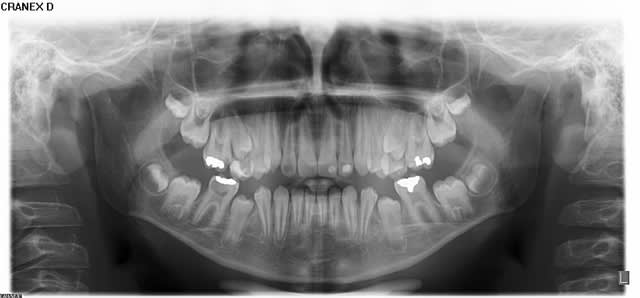

Quels sont les contre-indications absolues ? Hypodivergence, agénésie des 8 ou germes non visibles, quoi d'autre ?

Qui ferait quoi dans le cas ci-dessous : 11 ans, patient en classe I, normodivergent, hygiène médiocre, très coopérant au fauteuil. 36 présente une carie similaire en lingual. Ces deux dents sont vitales.

De plus, les 5 peuvent aussi rester bloquées par la bascule des 4 et 7... vu la pano... et les germes des 8 ont l'air pas mal...

Sans culpabiliser du tout, on peut dire que l'extraction des 4 six est à préférer à l'extraction de prémolaires en cas d'encombrement d'origine dento-dentaire et si les six sont particulièrement détruites mais comme même dans ce cas les extractions de prémolaires sont toujours jugées inopportunes par certains orthodontistes... il faut bosser avec un orthodontiste qui ose encore préconiser les extractions... ou alors faire une formation d'ortho pour prendre la décision en âme et conscience...

Il faut savoir que les cas d'ortho traités avec extraction de prémolaires permettent souvent de conserver les dents de sagesses...